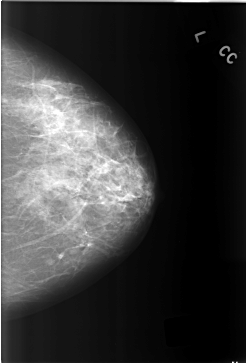

C_0304_1.LEFT_CC

LEFT_CC LINES 5800 PIXELS_PER_LINE 3928 BITS_PER_PIXEL 12 RESOLUTION 50 NON_OVERLAY

LEFT_MLO LINES 5792 PIXELS_PER_LINE 3968 BITS_PER_PIXEL 12 RESOLUTION 50 NON_OVERLAY